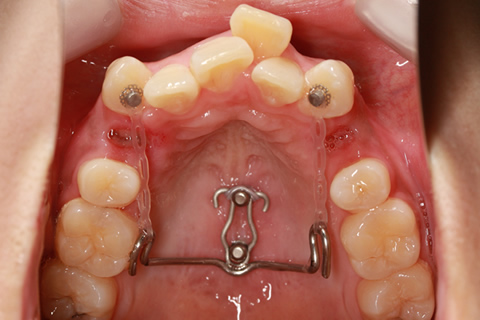

最新鋭の口蓋骨アンカースクリューを導入!

スピーディで確実な治療結果に期待!最新鋭の口蓋骨アンカースクリューを矯正治療に導入しました。まず痛そうですが、痛みはほとんどありませんのでご安心下さい。歯列不正を引き起こしている原因は本当に様々な要素が相まっています。歯の位置、歯の大きさ、顎の幅、上下のアゴの位置関係、etc...矯正治療開始される患者様の2割はかなりシビアな状態であり、今までの矯正治療では100%の状態までキレイに治せないものでした。

初期のアンカースクリューは固定源として使うだけのものでしたが、矯正歯科界を代表する重鎮の先生方により進化していき、上顎の口蓋正中部に埋入したスクリューに、専用ワイヤーを装着することで、大臼歯のコントロール、前歯部のリトラクション、他多くのメカニクスのアンカレッジとして使用できるようになりました。

初期に開発されたアンカースクリュー